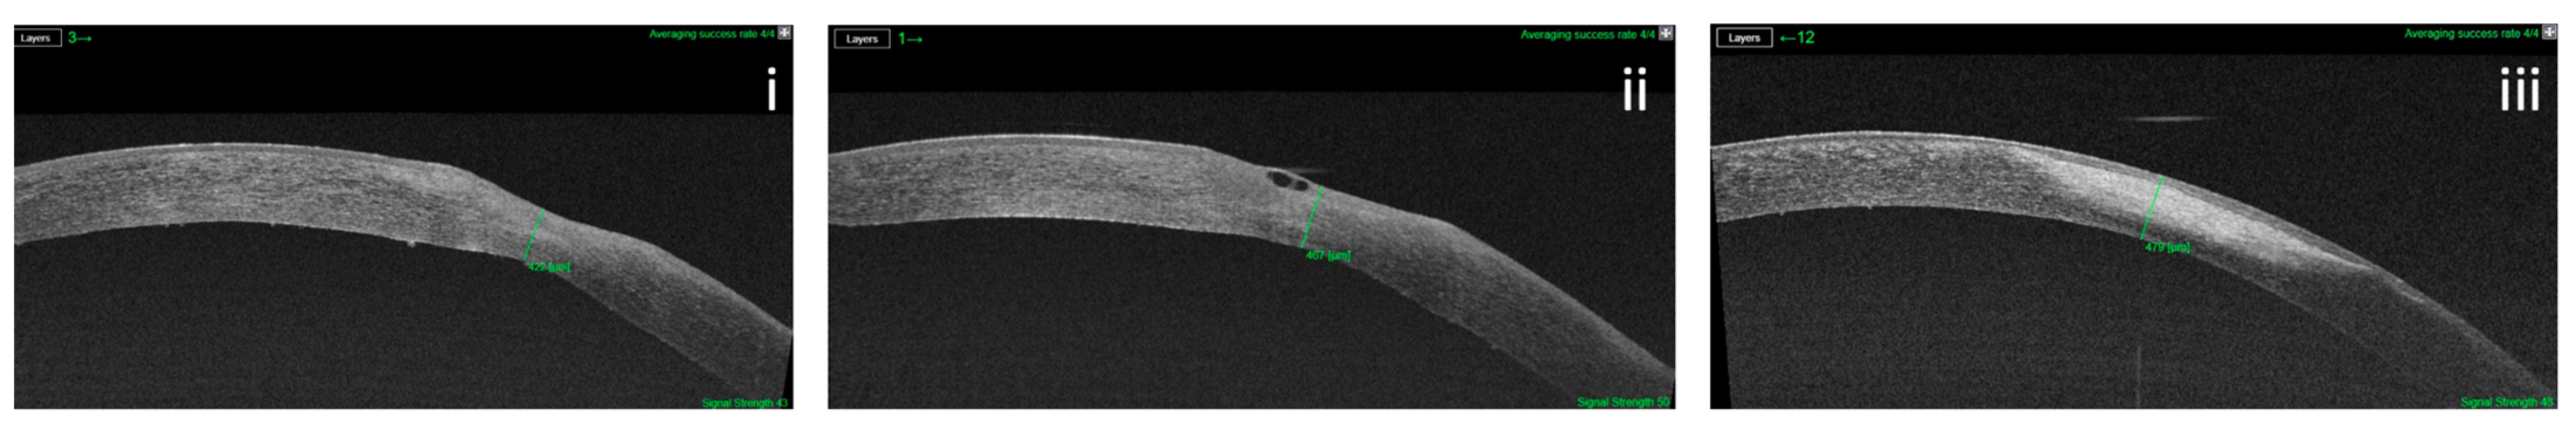

3.2. Corneal Thickness